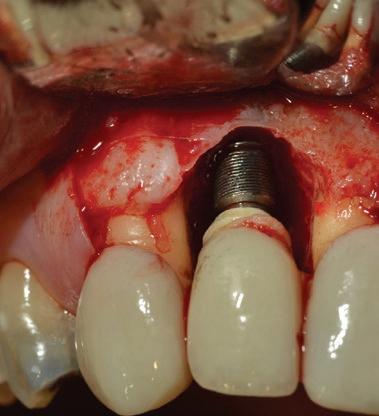

La gestion de l’alvéole post-extraction constitue un défi fréquent en pratique clinique. Lorsqu’un traitement implantaire est envisagé, le contrôle de la résorption osseuse verticale et horizontale devient essentiel afin de préserver les conditions idéales pour un futur positionnement implantaire.

L’objectif de ce module est de permettre une approche rigoureuse de la préservation alvéolaire, en vue d’optimiser le positionnement tridimensionnel de l’implant et de faciliter l’intégration fonctionnelle et esthétique de la restauration prothétique.

Étapes chirurgicales :

Survol des étapes chirurgicales liées aux différents types de restaurations